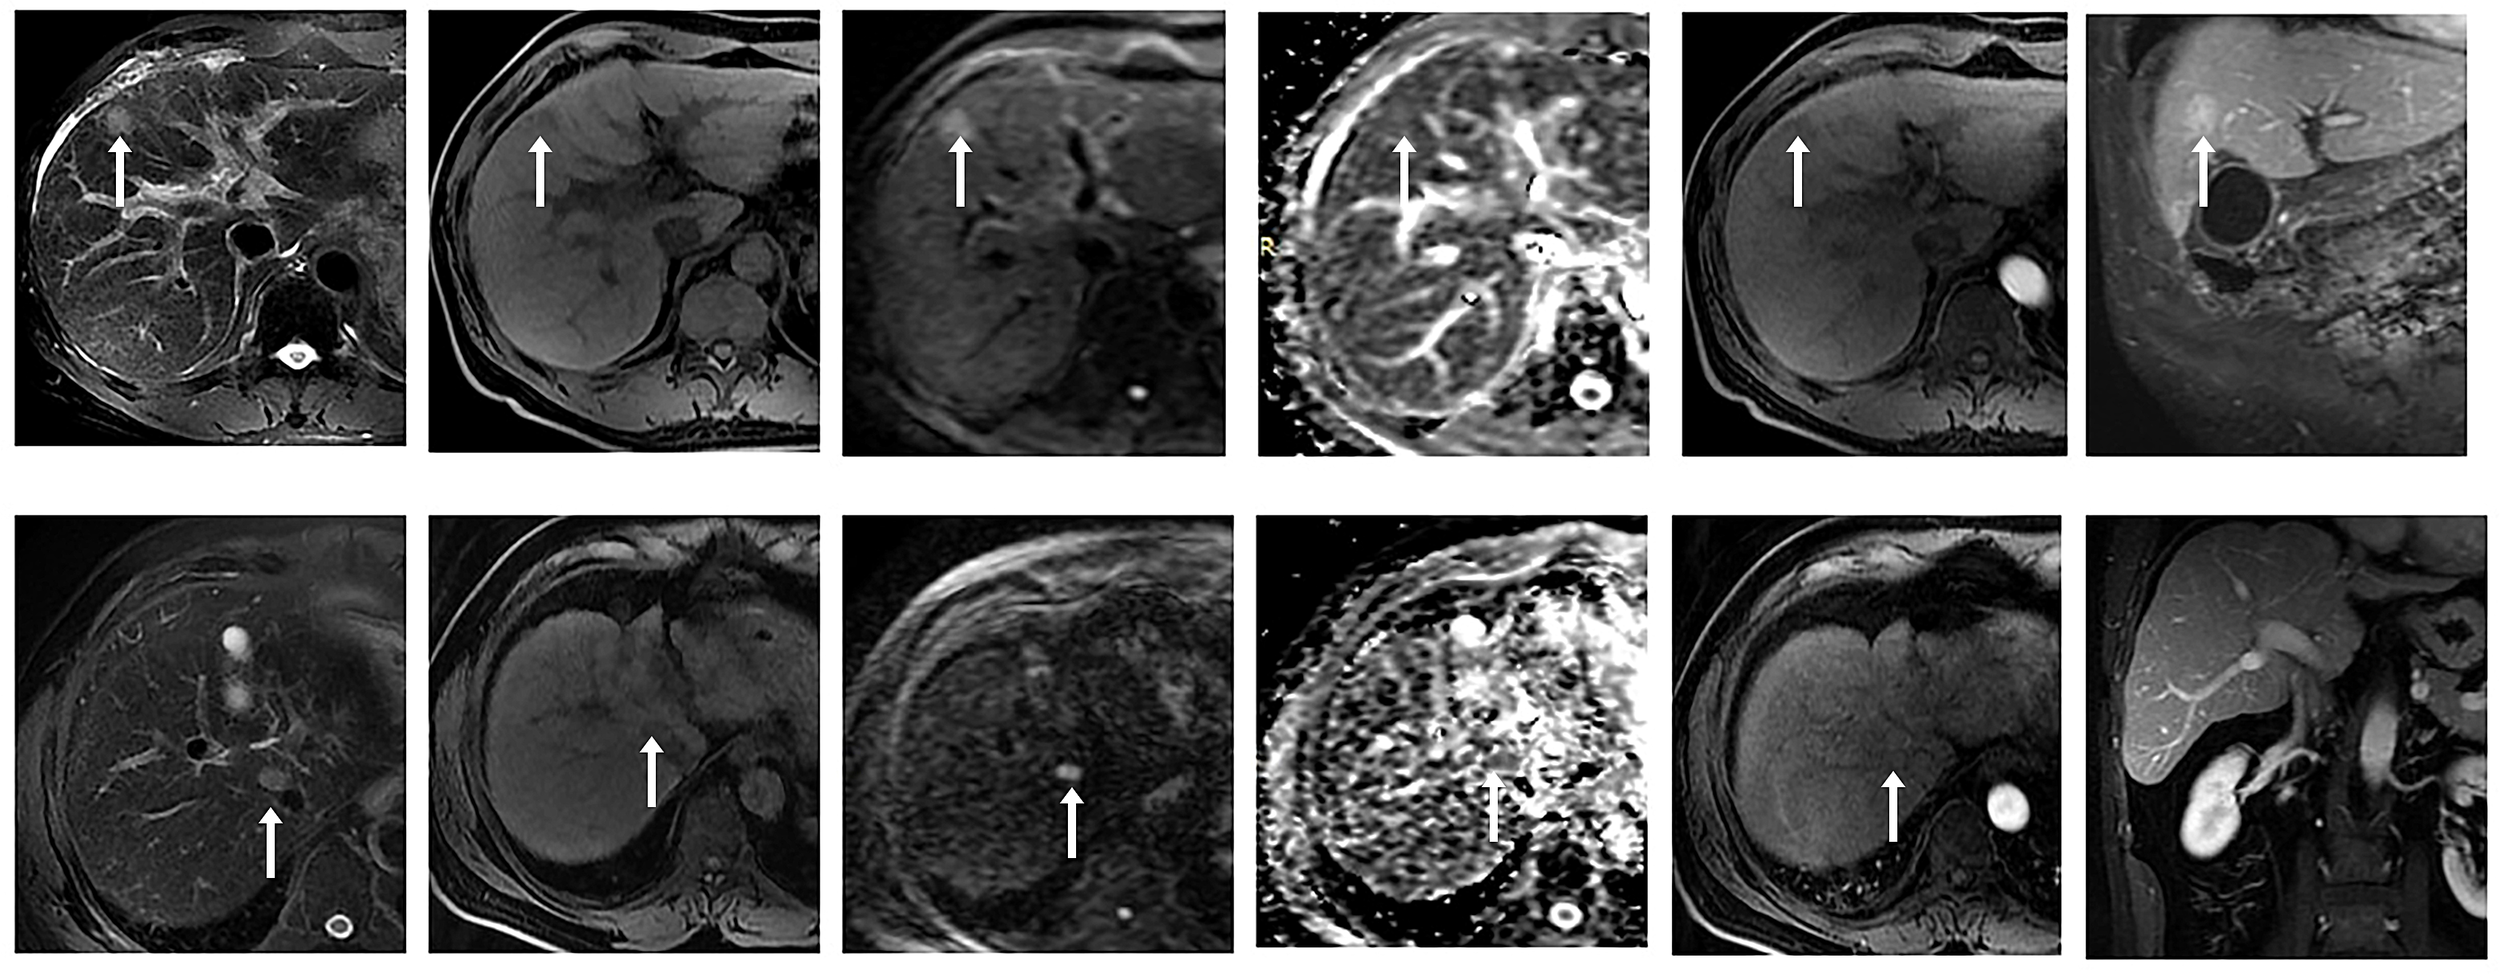

There were 135 nodules in 88 patients, according to the 2018 version of LI-RADS criteria, 13 nodules not in the LR-3 category were excluded (4 LR-1, 8 LR-2), and the remaining 122 nodules were in the LR-3 category, which were included in our study. Results analysis showed that these nodules included 54 malignant nodules (HCC, n = 49; ICC, n = 2; cHCC-CC, n = 3) and 68 benign nodules (DN, n = 12; RN, n = 13; FNH, n = 3; Hemangioma of liver, n=20; Inflammatory foci in liver, n=14; Hepatic adenoma, n=5; Lipoma, n=1). Conscientious lesions and malignant lesions assessed as LI-3 grade are shown in Figure 2.

Figure 2

① Male, 53 years old, chronic hepatitis (B) A small nodule with a long diameter of about 1.8 cm in the left medial lobe of the liver showed high signal intensity on DWI (b value = 800 mm ²/s) and slightly high signal intensity on ADC, with a mean ADC value of about 1.409 × 10 - 3 mm ²/s. No significant enhancement was observed in the arterial phase after enhancement, and significant enhancement was observed in the portal venous and delayed phases. Postoperative pathology confirmed regenerative nodules (RN). ② A 58-year-old male patient presented with a history of chronic hepatitis B and cirrhosis. A small nodule with a long diameter of about 1.5 cm was observed at the junction of the right anterior lobe and caudate lobe of the liver, with low signal intensity on T1WI and slightly high signal intensity on T2WI. DWI (b value = 800 mm ²/s) and ADC maps showed limited diffusion, with an ADC mean value of about 0.983 × 10- ³ mm ²/s. After enhancement, non-annular mild enhancement was observed in the arterial phase, isointensity was observed in the delayed phase, and no non-peripheral clearance or capsule-like enhancement was observed. Postoperative pathology confirmed hepatocellular carcinoma (HCC).